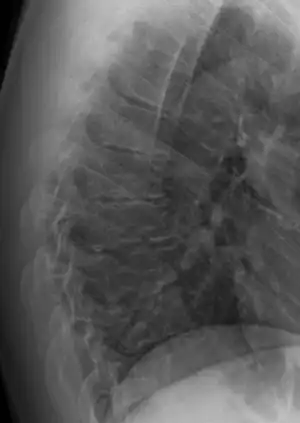

Diagnosis is typically by medical imaging. The degree of kyphosis can be measured by Cobb's angle and sagittal balance.

Scheuermann's disease on lateral CT of the T spine